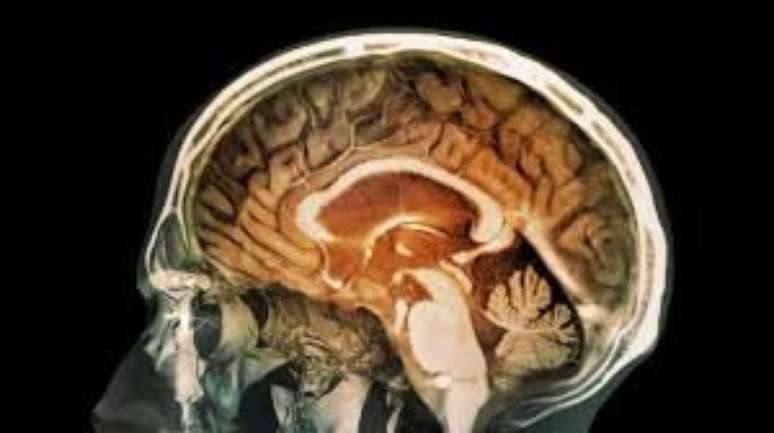

Ciência ainda não conseguiu decifrar o funcionamento do cérebro

Foto: BBC News Brasil

Ribeiro - Depende da vez. É uma situação de muito insight. Se eu te disser "mexa o polegar direito", você mexe. Mas se for para ativar o hipocampo esquerdo, você não consegue, você não sabe onde ele está.

Quando a gente está numa experiência de ayahuasca, você consegue visualizar onde está o hipocampo esquerdo. Se isso é de fato o hipocampo esquerdo ou só uma ilusão, eu não sei.

Mas é uma situação em que se consegue simular o próprio funcionamento cerebral. No fundo, um cientista está sempre pensando em ciência. O que será que está acontecendo no meu cérebro para que eu possa estar vendo isso?

Aí entra a questão da interpretação. A pessoa que está na religião vai dizer: "eu vi um espírito". Enquanto um cientista materialista vai dizer: "eu vi uma representação daquela entidade que habita meu cérebro".

A gente já entendeu como o coração funciona. Por que a gente ainda não entendeu como o cérebro funciona? Porque é mais complicado. O que é a consciência?

Esta é a geração que finalmente vão conseguir entender o que é a consciência. Poderão dizer que na tradição hindu já conhecem a consciência faz tempo. Mas não nos termos da biologia, da química, da física. Essa tradução está sendo feita agora.